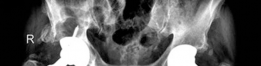

Revision THA Acetabulum Paprosky Type IIIA. ARMD with Metallosis with Severe Periacetabular Osteolysis and Co…

Case Title: The Use of Acetabular Augments for Revision Total Hip Arthroplasty Demographics Age: 71 years old…